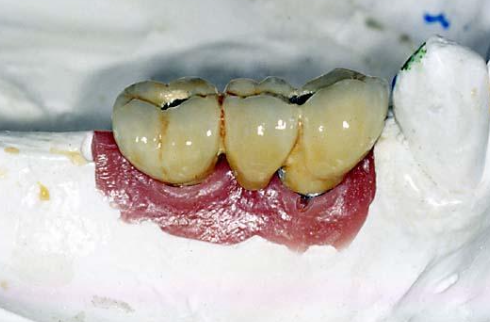

Lab will make buccal / lingual groove to verify seating of restoration

When should stone model contouring be done?

On bone level implants when fabricating metal abutments / PFM and FGC restorations

What are the steps for finishing the restoration?

Remove excess acrylic resin/ protemp

Fill any voids and do final contouring

Make sure the restoration is in emergence profile

Check occlusion / proximal contacts

Polish